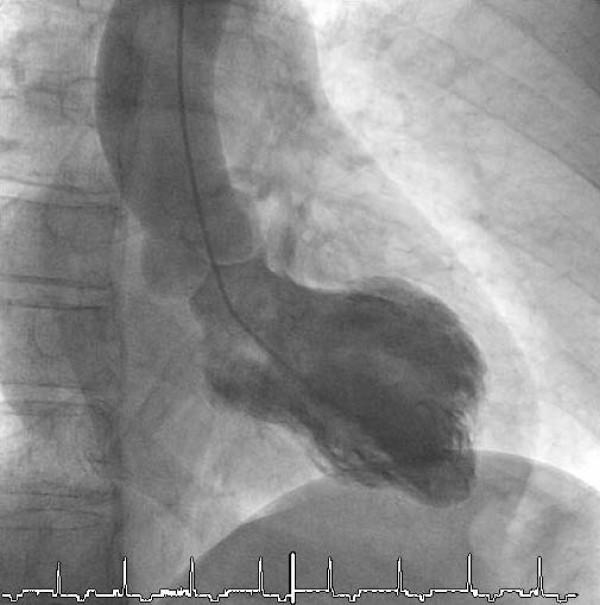

Takotsubo cardiomyopathy was first described in Japan and is characterized by transient left ventricular apical ballooning in the absence of a significant coronary artery disease.Caused by the clinical presentation including chest pain, electrocardiographic changes and elevated myocardial markers this syndrome is frequently misdiagnosed as an acute coronary syndrome. Recurrences of Takotsubo Cardiomyopathy, especially in variant regions of the left ventricle are rareWe describe a midventricular form of Takotsubo Cardiomyopathy as a recurrence 1 year after typical apical ballooning.

应激性心肌病最早在日本被描述,其特征是在无显著冠状动脉疾病的情况下出现短暂的左心室心尖部气球样变。由于临床表现包括胸痛、心电图改变和心肌标志物升高,该综合征常被误诊为急性冠状动脉综合征。应激性心肌病的复发,尤其是在左心室的变异区域,较为罕见。我们描述了一例应激性心肌病心室中部型,为典型心尖部气球样变1年后复发的病例。